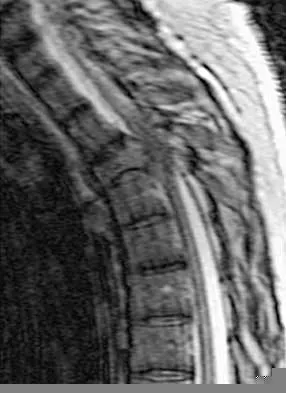

A 60-year-old woman with a history of breast cancer has progressive paraparesis. The MRI scan is shown in Figure 28. What form of management is most likely to restore or maintain ambulation?

Surgical decompression and stabilization have been shown to be the most effective means of improving neurologic function. Decompression is most reliably done from the side of the compression, which is anterior in this patient. Harrington KD: Metastatic tumors of the spine: Diagnosis and treatment. J Am Acad Orthop Surg 1993;1:76-86.